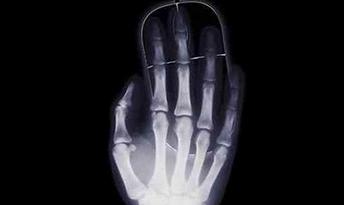

3D打印在醫(yī)療領(lǐng)域的進(jìn)步是一個(gè)全球化的現(xiàn)象。世界各地的醫(yī)生將3D打印與手術(shù)相結(jié)合,科學(xué)家們也以驚人的速度研究生物3D打印,毫無疑問,未來的醫(yī)學(xué)世界必將會被3D打...